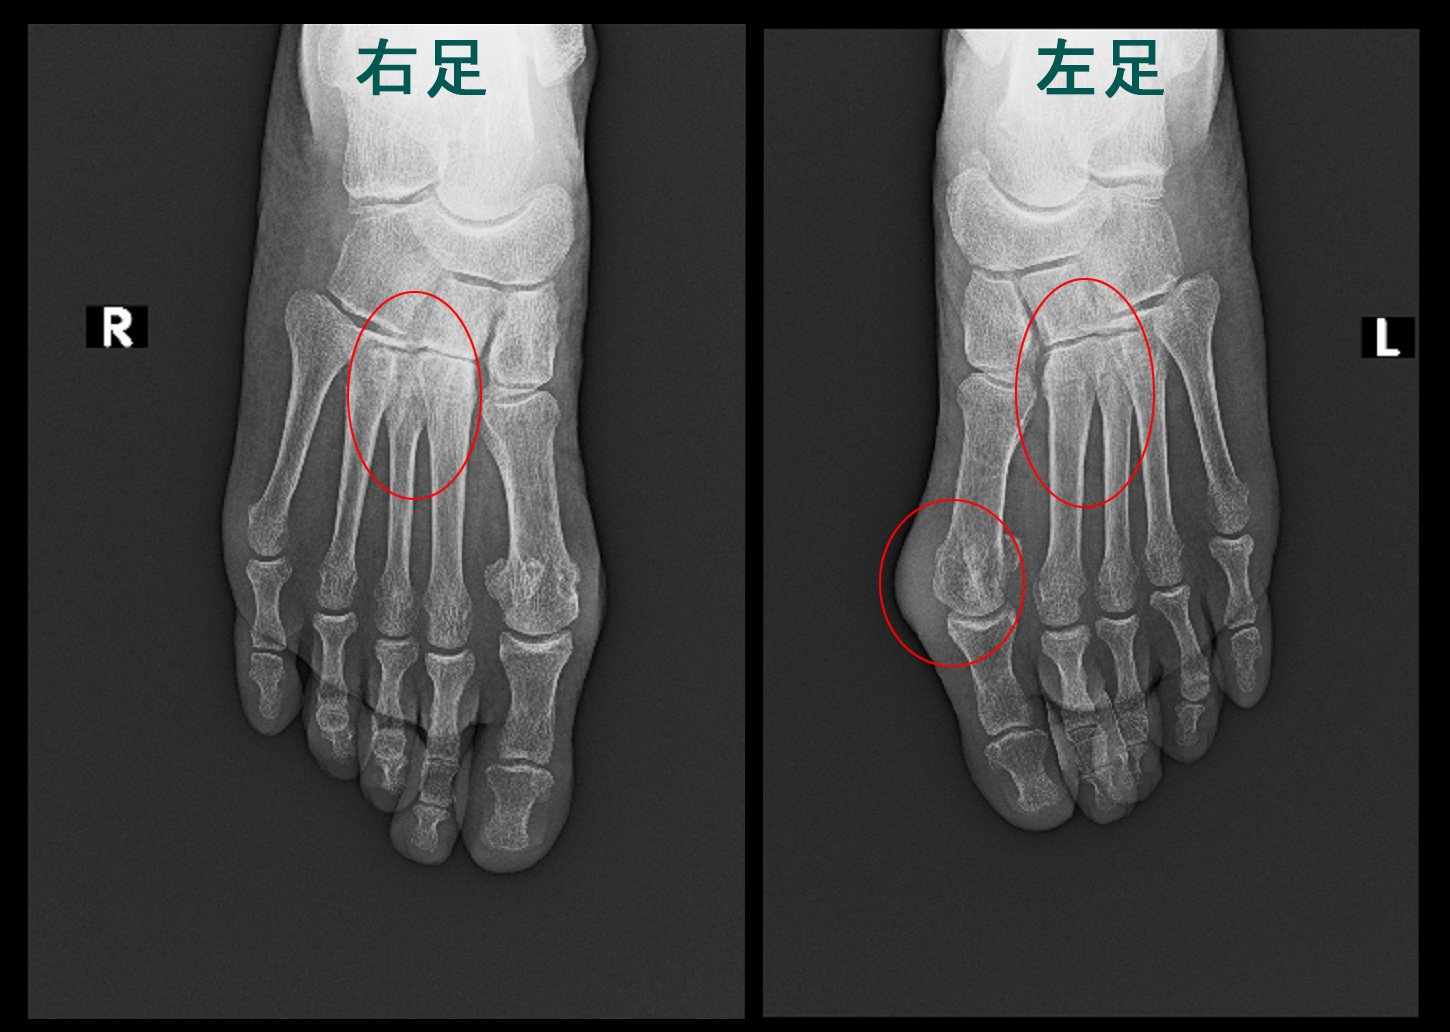

4月8日に当院を受診されました。右足背部痛の他にも、左足背部痛と第1趾MP関節(指のつけ根の関節)痛も訴えられました。

当院を受診された時は診断されて加療した経過の中であり、手指の関節痛や手関節痛の訴えはなく、両側足部痛の訴えであり、比較的まれなリウマチの状態でした。

右足背部の痛みの程度を確認すると、VAS10!(=最高に痛い)とのことでした。初診日の血液検査でリウマチ因子は157(正常は15以下)、抗CCP抗体という近年RAに特徴的な血液検査は497.7(正常は4.5以下)で、リウマチで間違いない結果です。